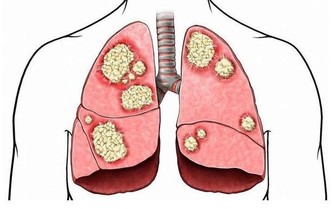

研究認為,苯是染髮劑中最基本的化學物質,對造血系統具有強烈毒性。染髮劑使用一個階段后,苯會沿頭髮浸入頭皮毛細血管,破壞造血系統,引起頭暈、乏力、皮下、內臟和腦出血,更加嚴重的是誘發癌症。近年來,醫學界常使用「染髮白血病」這個名詞,表明了染髮與白血病的關係。

染髮劑一般分為暫時性染髮劑、半持久性染髮劑和持久性(氧化型)染髮劑,絕大多數人使用的是持久性染髮劑。持久性染髮劑含有對苯二胺(PPD),這是目前使用最廣泛的著色劑成分。PPD是一種公認的致癌物質,流行病學調查顯示它可以增加患膀胱癌的風險,特別是黑色染髮劑,含PPD的量相對較高。

美國和加拿大一項研究調查了766名成人白血病患者和623名沒有得過白血病的健康人,與沒有使用染髮劑的人比較,使用持久性染髮劑和半持久性染髮劑者患急性白血病的危險性較高。